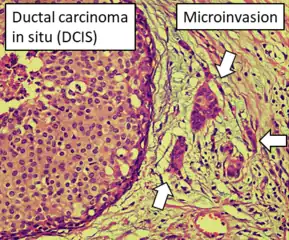

DCIS with microinvasion, defined as focus of invasive cancer measuring up to 1.0 mm in size.[26]

DCIS with microinvasion, defined as focus of invasive cancer measuring up to 1.0 mm in size.[26] Immunohistochemistry for calponin in ductal carcinoma in situ, highlighting myoepithelial cells around all tumor cells, thereby ruling out invasive ductal carcinoma.

- Hayward, M.K.; Louise Jones, J.; Hall, A.; King, L.; Ironside, A.J.; Nelson, A.C.; et al. (2020). "Derivation of a nuclear heterogeneity image index to grade DCIS". Comput Struct Biotechnol J. 18: 4063–4070. doi:10.1016/j.csbj.2020.11.040. PMC 7744935. PMID 33363702. - ↑ Image annotation by Mikael Häggström, MD, using source image from:

Moatasim A, Mamoon N (2022). "Primary Breast Mucinous Cystadenocarcinoma and Review of Literature". Cureus. 14 (3): e23098. doi:10.7759/cureus.23098. PMC 8997314. PMID 35464581.

- "This is an open access article distributed under the terms of the Creative Commons Attribution License CC BY 4.0."

Source for microinvasion: "Protocol for the Examination of Resection Specimens from Patients with Ductal Carcinoma In Situ (DCIS) of the Breast, Version: 4.4.0.0. Protocol Posting Date: June 2021" (PDF). College of American Pathologists. - ↑ Image by Mikael Häggström, MD.